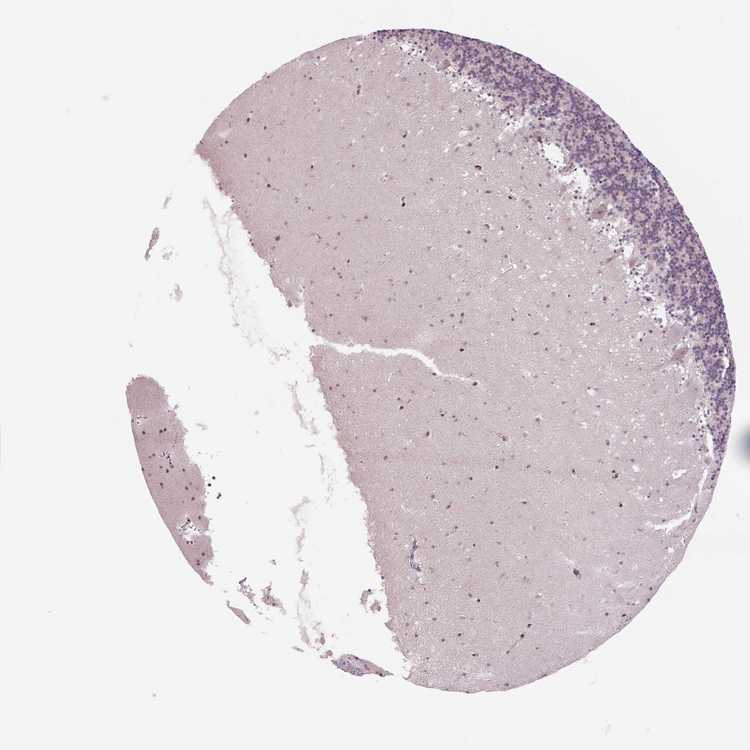

BRAIN CEREBELLUM Show tissue menu

CEREBELLUM - Expression summary

Protein expression

Cerebellumi

On the top, protein expression in current human tissue, based on all annotated cell types, is reported with the units not detected (n), low (l), medium (m) and high (h). Underneath, protein expression in each annotated cell type are reported using the same units.

Protein expression data is based on knowledge-based annotation. For genes where more than one antibody has been used, a collective score is set.

If knowledge-based annotation could not be performed for a gene, no data is displayed here. View antibody staining data further down this page.

h

m

l

n

Cells in granular layer: Not detected

Cells in molecular layer: Not detected

Purkinje cells: Not detected

CEREBELLUM - Antibody stainingi

Antibody staining in the annotated cell types in the current human tissue is reported as not detected, low, medium, or high, based on conventional immunohistochemistry profiling in selected tissues. This score is based on the combination of the staining intensity and fraction of stained cells.

Each image is clickable and will lead to virtual microscopy that enables deeper exploration of all samples and also displays staining intensity scores, fraction scores and subcellular localization as well as patient and tissue information for each sample.

Antibody HPA069497Antibody CAB002786Antibody CAB069881

Purkinje cells Not detectedNot detectedNot detected

Cells in granular layer Not detectedLowNot detected

Cells in molecular layer Not detectedNot detectedNot detected